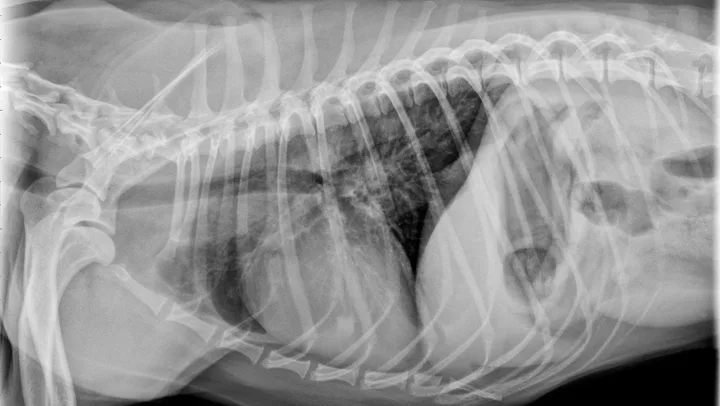

Dogs with bacterial pneumonia are typically presented with acute-onset coughing, lethargy, inappetence, and/or respiratory distress. An inflammatory leukogram and pyrexia, although common, are not always present. Radiographs may reveal an interstitial-to-alveolar pattern with a cranioventral distribution (Figure 1). Atypical distributions can also occur.5

FIGURE 1

(A) Bronchopneumonia. Cranioventral distribution of alveolar disease with air bronchograms. (B) A patchy distribution can be observed on the lateral projection. The changes overlying the heart may be missed in subtle cases.